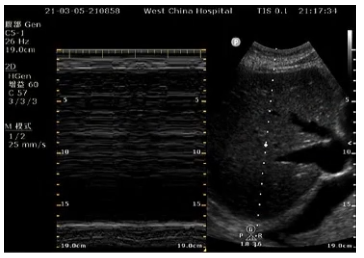

辅助检查:入科第2天行气管镜检查示左肺通畅,右肺大量黄色脓痰(35 ml)(图1)。再行肺部超声检查示右肺点有明显的碎片征,提示右肺实变(图2)。膈肌超声检查示患者右侧膈肌不动,对EDP无反应(图3)。

图3 膈肌超声检查

各项检查均提示患者右肺存在问题,且患者右侧膈肌对EDP无反应,是何原因?

查阅文献发现,高位颈髓病变可导致肺实变和肺不张,机制为:①外周交感兴奋性降低;②呼吸肌力降低;③咳嗽反射降低(图4)。故进一步考虑此例患者为外周神经疾病病变引起的单侧膈肌不动,目标为气道管理、改善肺充气、膈肌管理。